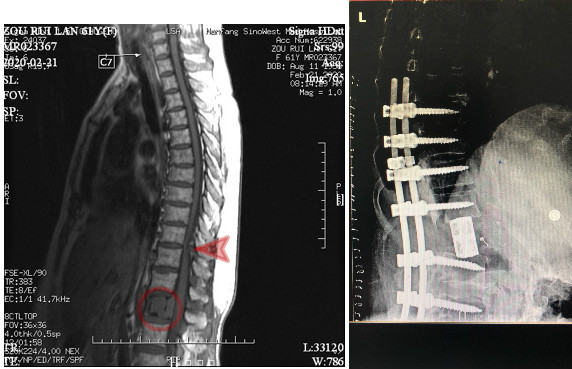

图左:术前MR示腰椎肿瘤(圆圈处)、胸椎狭窄(箭头所指)

图右:术后X光,病变脊椎切除,代以人工椎体。

手术整整进行了11个小时,在黄刚主任专业细致的操作下,邹阿姨最终有惊无险的完成了整台手术,成功对腰椎肿瘤行根治性切除,手术同时进行了胸椎板切除、椎管减压术,一并解除了邹阿姨胸椎管狭窄脊髓受压的病痛。

术中出血1500ML,远低于平均出血量,且术后疗效满意,脚底麻木完全缓解,排尿困难已解决,经过一个周期的放疗后,邹阿姨已于日前出院。